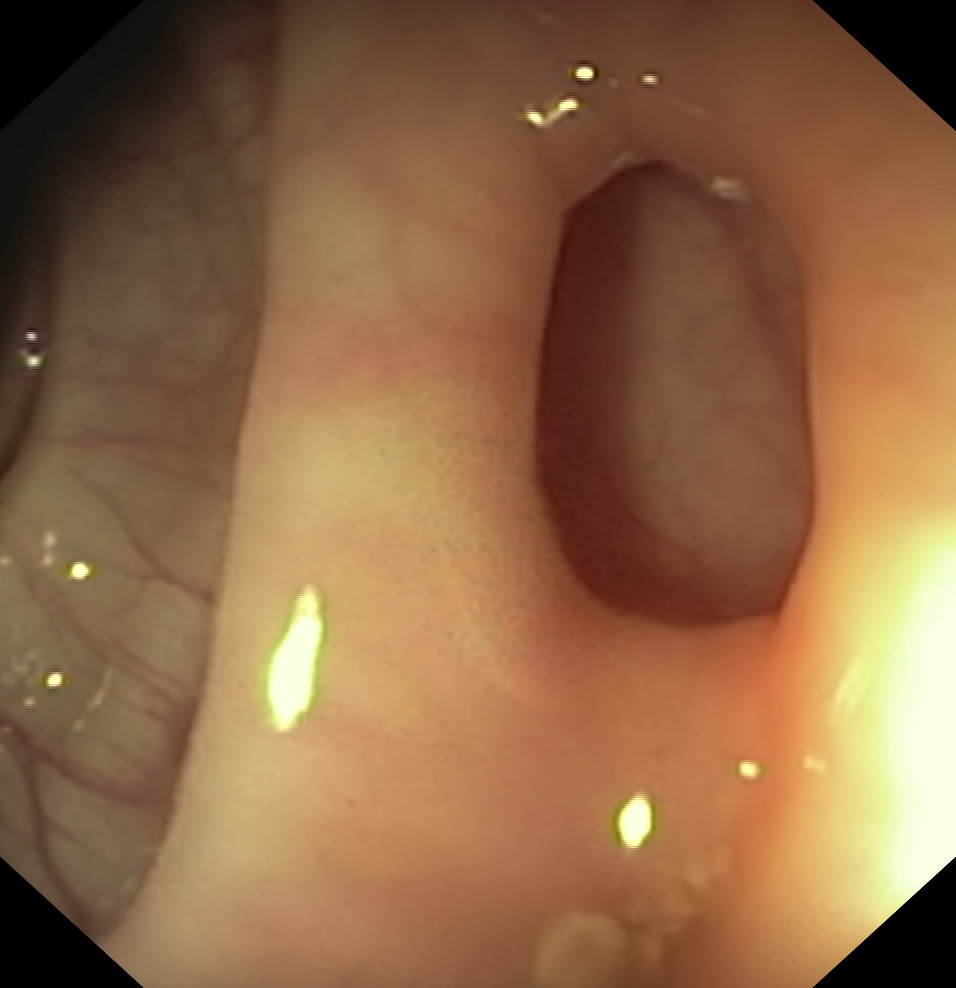

Uchyłki